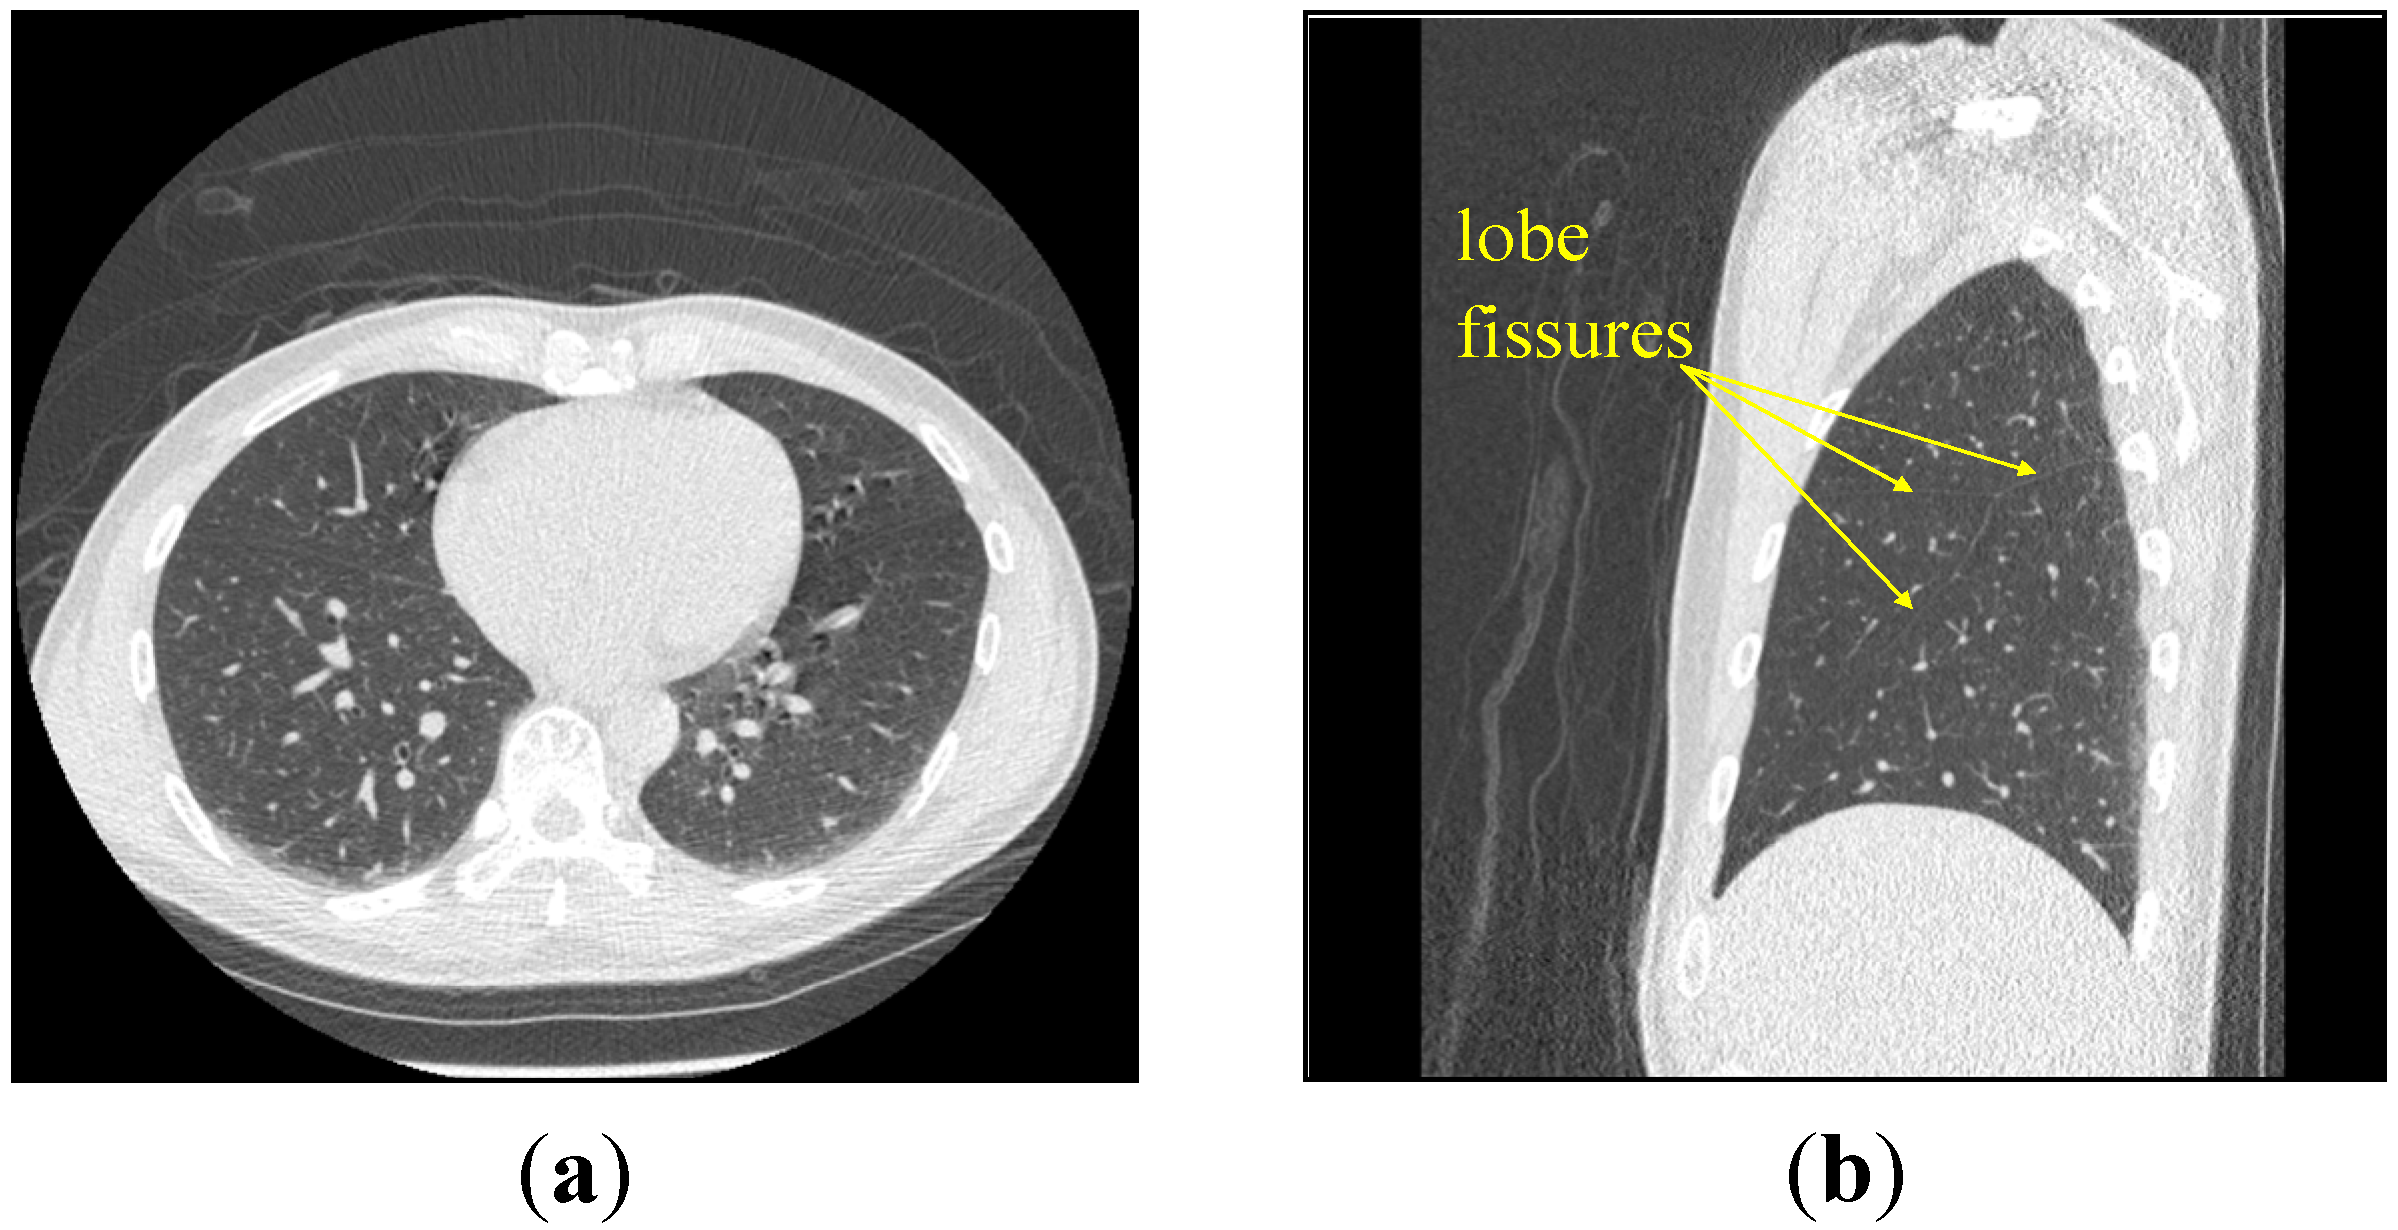

3.1. Data Acquisition